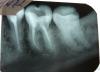

gea_rus Опубликовано 7 марта, 2011 Поделиться Опубликовано 7 марта, 2011 Длительное время лечу 36 зуб. Второй врач перелечила каналы, но осталась боль при накусывании. Ноет на холодное. Был вариант, что болит 5 - ка. Пролечили и её. Назначали Флюктуации №3 было незначительное улучшение, но затем всё вернулось. В настоящее время убрали постоянную пломбу. Поставили временную. "Будем наблюдать". Большая просьба, посмотрите, пожалуйста, есть ли за чем ещё наблюдать. Может пора уже просто убрать и не мучиться. Фото в хронологической последовательности. Ссылка на комментарий

Bier Опубликовано 7 марта, 2011 Поделиться Опубликовано 7 марта, 2011 мне кажется, что недопломбировка в медиальном корне 36з Ссылка на комментарий

DokDent Опубликовано 7 марта, 2011 Поделиться Опубликовано 7 марта, 2011 Длительное время лечу 36 зуб. Второй врач перелечила каналы, но осталась боль при накусывании. Ноет на холодное. Был вариант, что болит 5 - ка. Пролечили и её. Назначали Флюктуации №3 было незначительное улучшение, но затем всё вернулось. В настоящее время убрали постоянную пломбу. Поставили временную. "Будем наблюдать". Большая просьба, посмотрите, пожалуйста, есть ли за чем ещё наблюдать. Может пора уже просто убрать и не мучиться. Фото в хронологической последовательности.Как зуб реагирует на холодное?:боль слабая кратковременная,умеренная кратковременная,резкая кратковременная,выраженная боль длительностью более 5 сек.,более 10 сек.,начинается через время и медленно прекращается.Правильно Вам доктор Bier сказал-каналы в медиальном корне надо бы перелечить. Ссылка на комментарий

juli63 Опубликовано 7 марта, 2011 Поделиться Опубликовано 7 марта, 2011 честно говоря, мне и дистальный канал не очень нравиться... Ссылка на комментарий

Scrabble Опубликовано 7 марта, 2011 Поделиться Опубликовано 7 марта, 2011 В дистальном корне 2 канала-обтурирован один. Я бы советовала переделать. Ссылка на комментарий